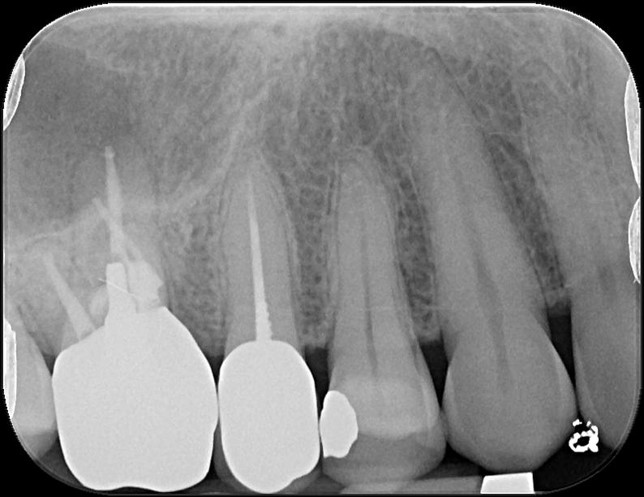

治療前,第一大臼齒根尖病變

顯微根管重治療